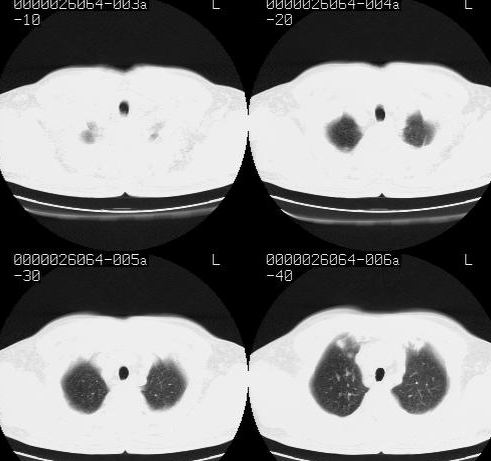

标题: CT15869:男性,71岁,因咳嗽而就诊,请讨论右上肺病变性质 [打印本页]

标题: CT15869:男性,71岁,因咳嗽而就诊,请讨论右上肺病变性质

患者,男性,71岁,因咳嗽而就诊,

典型的右肺中心性肺癌并纵隔淋巴结转移

考虑右肺中心性肺癌并右肺门及纵隔淋巴结转移。

1,右肺中心型ca,气管隆突旁淋巴结转移。

2,右膈明显抬高,建议肝脏扫描排除转移或原发灶。